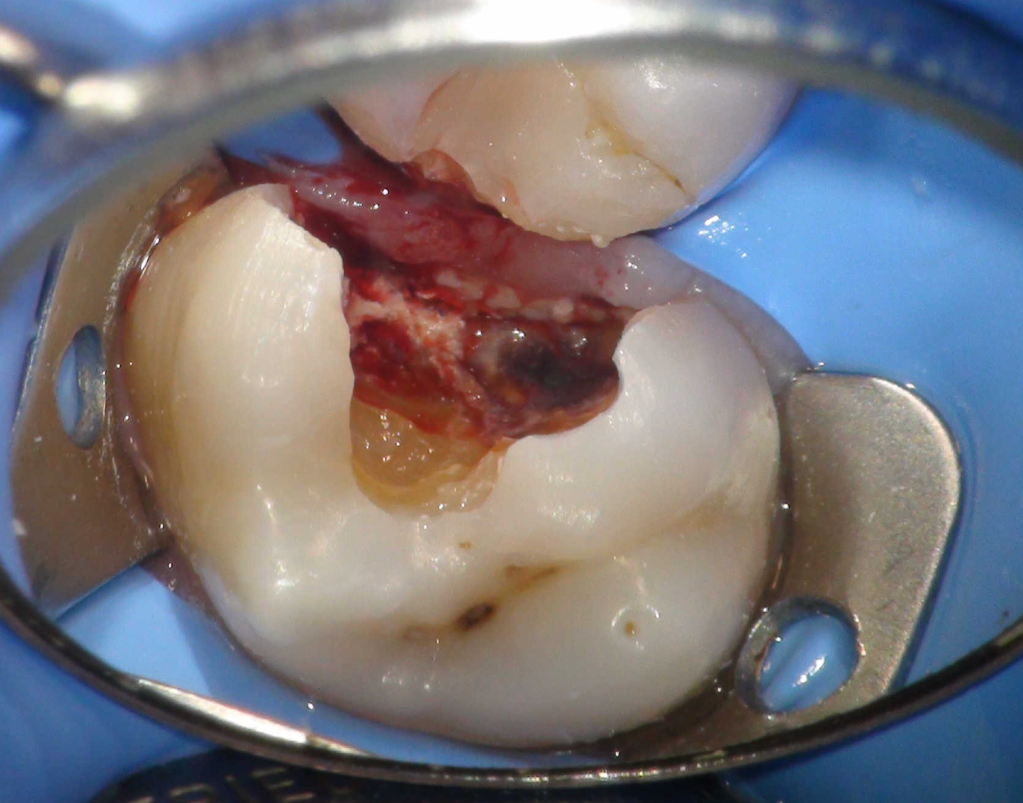

Pulpotomía biodentine + reco preendio